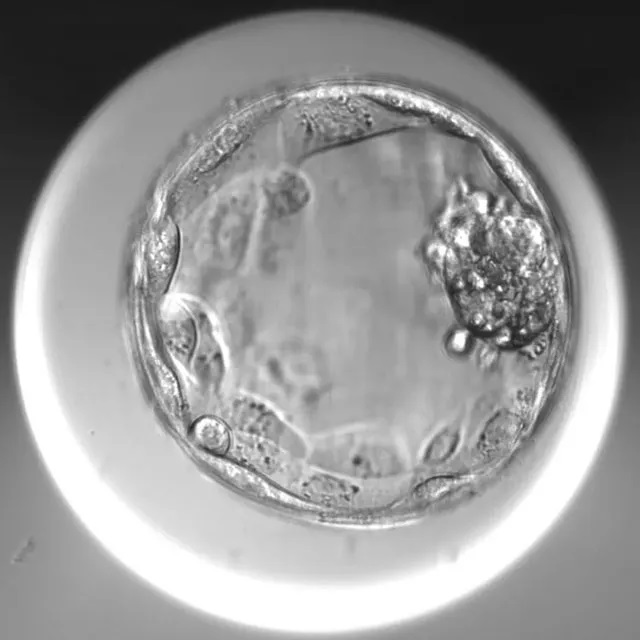

优质囊胚                可用囊胚

所以,哪怕评分蕞高的胚胎也可能是异常的胚胎 (比如染色体异常),而评分低的胚胎也可能是一个正常健康有发育潜能的胚胎。